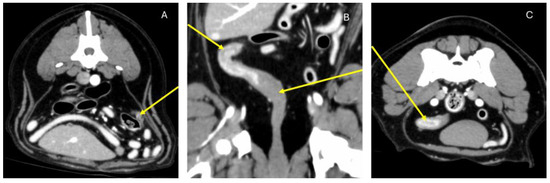

2. Case History